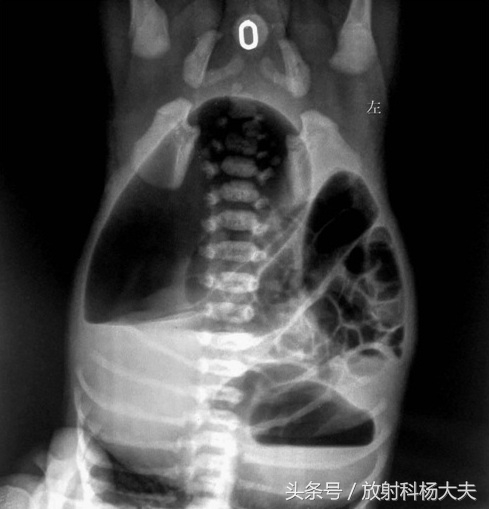

小周的孩子出生时产科护士给予常规检查,发现小宝宝没*眼屁**(医学专业术语:先天性肛门闭锁),没有大便。没*眼屁**怎么办。赶紧做手术吧,不行,必须得先去放射科拍个腹部倒立位及倒立侧位。绝大多数人拍腹平片都是立位的,这个病为什么要拍倒立位呢?原来,是为了看看直肠充气盲端与肛门隐窝距离有多大,为手术治疗提供依据。

倒立腹平片,观察闭锁端情况